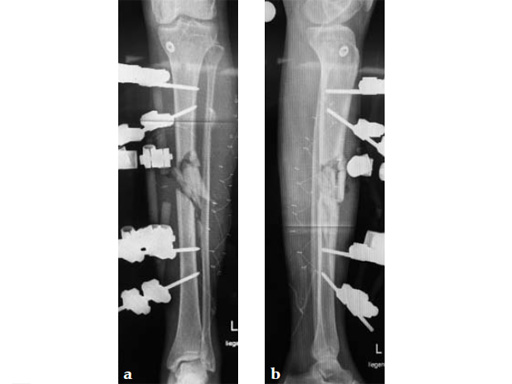

Case 1: A 33-year-old man with a third degree open fracture of his left tibia was initially treated with an external fixator and unilateral compartment release. He had undergone ACL reconstruction in the past.